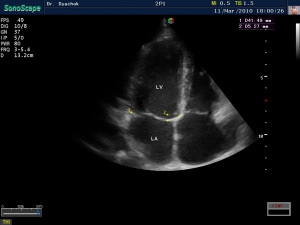

- Двухмерная. При выполнении такого типа УЗИ получают две проекции изучаемой области. Лучи посылаются с частотой ориентировочно 30 раз в секунду перпендикулярно друг другу. Получают объемное изображение, демонстрирующее порядок движения анализируемых структур.

Эхо сердца, как уже говорилось ранее, основывается на передаче ультразвуковых импульсов, которые, отражаясь от преград, преобразовываются в электрические сигналы, которые принимаются преобразователем. Картинка представляется на экране компьютера в объемном виде. Такая форма обследования считается более прогрессивной и способна предоставить больший объем сведений, например, о «застрявших» сгустках крови у больного, перенесшего приступ.

С помощью УЗИ сердца можно подробно исследовать структуру этого органа и оценить его способность к перекачиванию крови. С помощью Эхо КГ можно увидеть размер всех камер сердца, толщину стенок и перегородок, площадь отверстий клапанов и диаметр магистральных сосудов, отходящих от сердца, скорость тока крови через клапаны, объем крови, выбрасываемой камерами сердца.